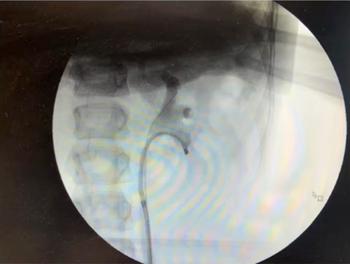

This video shows a case of semi-rigid ureteroscopy with laser lithotripsy for ureteral stone in a child, who is rendered stone free without pre-stenting.

This video of bilateral ureteroscopy in a 16-year-old male with cystinuria highlights several pragmatic strategies for efficient ureteroscopy while minimizing ionizing radiation.